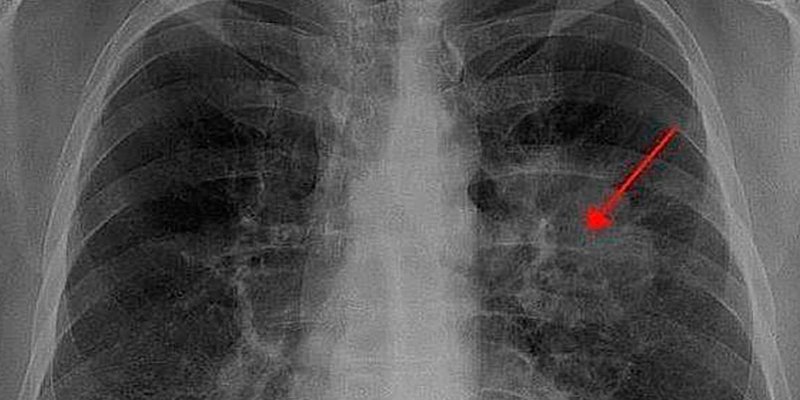

En el año 2015 se diagnosticaron en nuestro país 28.347 nuevos casos de cáncer de pulmón, tipo de tumor que, responsable solo en 2014 del deceso de 21.220 españoles, presenta la mayor mortalidad asociada a cualquier enfermedad oncológica. De hecho, y cada año, los decesos provocados por este tumor -hasta 1,8 millones en todo el mundo- superan a las que causan conjuntamente los cánceres de mama, próstata y colorrectal. La razón se explica fundamentalmente por el retraso en el diagnóstico de este tipo de cáncer y, sobre todo, por la falta de eficacia de las terapias actualmente disponibles. Sobre todo en las fases avanzadas de la enfermedad. Por tanto, se requiere con urgencia el desarrollo de tratamientos más efectivos. De ahí la importancia de un estudio llevado a cabo por investigadores del Centro Nacional de Investigaciones Oncológicas (CNIO) en Madrid, en el que se muestra que, cuando menos en modelos animales -ratones-, la eliminación por técnicas de ingeniería genética de la enzima c-Raf induce una regresión de los tumores de pulmón avanzados con mutaciones en el gen ‘KRAS’. Todo ello con unos mínimos efectos secundarios, lo que abre la puerta al posible desarrollo de tratamientos seguros y eficaces frente a esta devastadora enfermedad.